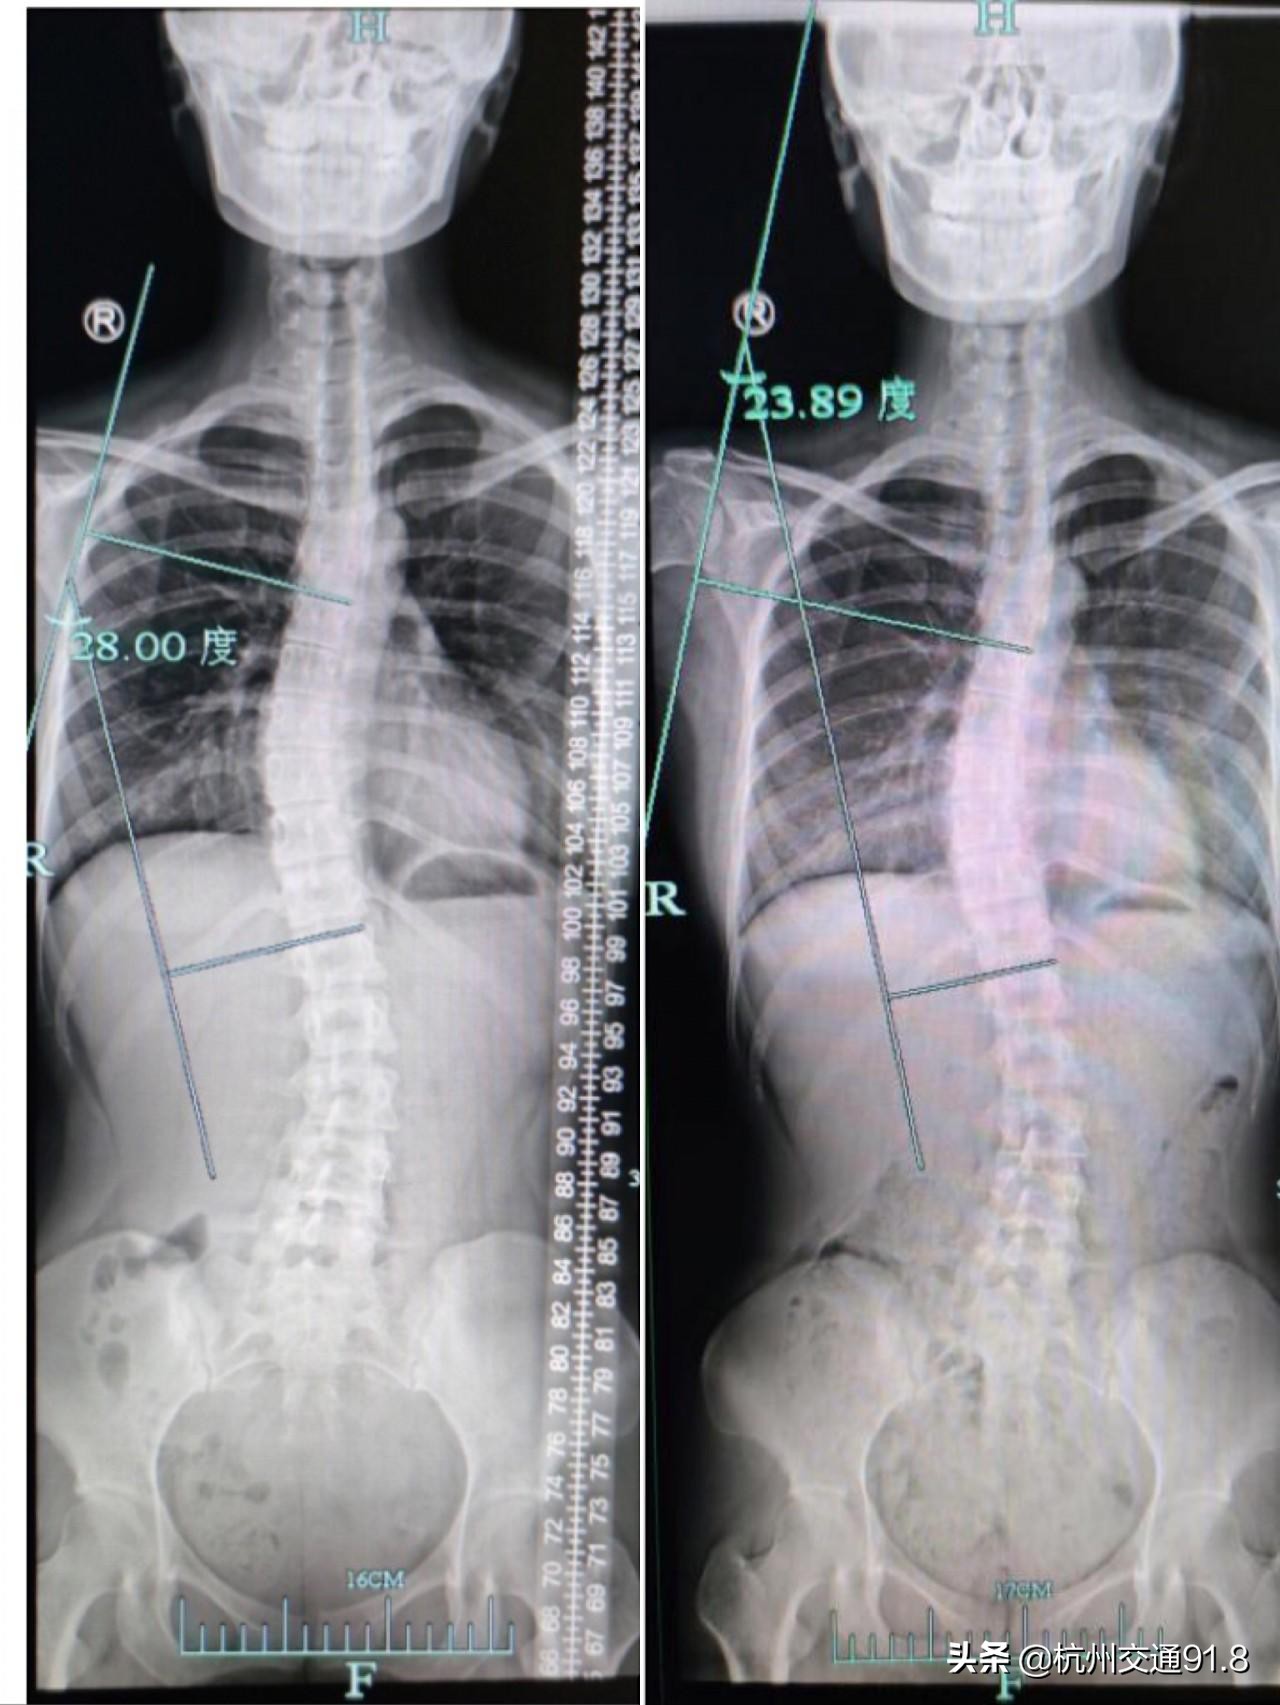

治疗前和治疗2个月后对比图